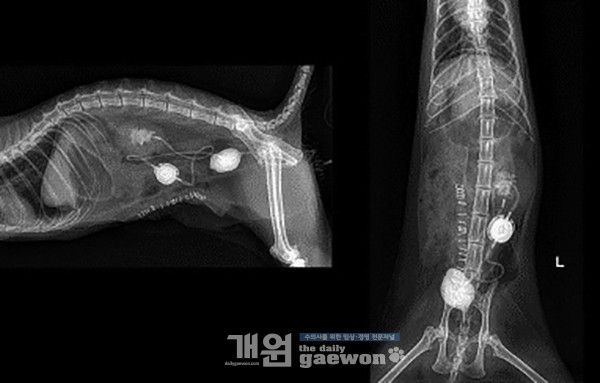

RI index는 8.3 정도로 측정됩니다. 위 환자는 왼쪽 신장에 SUB의 장착을 실시하였습니다(그림 10).

피하요관우회술의 부작용은 여러 가지가 있습니다(표 1). 피하요관우회술은 고양이 요관 폐색 환자에서 스텐트를 삽입하기 어렵거나 실패했을 때 지시가 됩니다.

SUB는 요관의 손상 없이 신우에서 방광으로 요의 흐름을 가져갈 수 있게 하는 장점이 있습니다. 이러한 점은 다른 수술 보다 환자에게 안전한 수술 옵션을 줄 수 있습니다.

결론적으로 SUB는 고양이 요관 결석 환자에게 적절한 치료 옵션으로써 적용할 수 있다고 생각됩니다. <完>